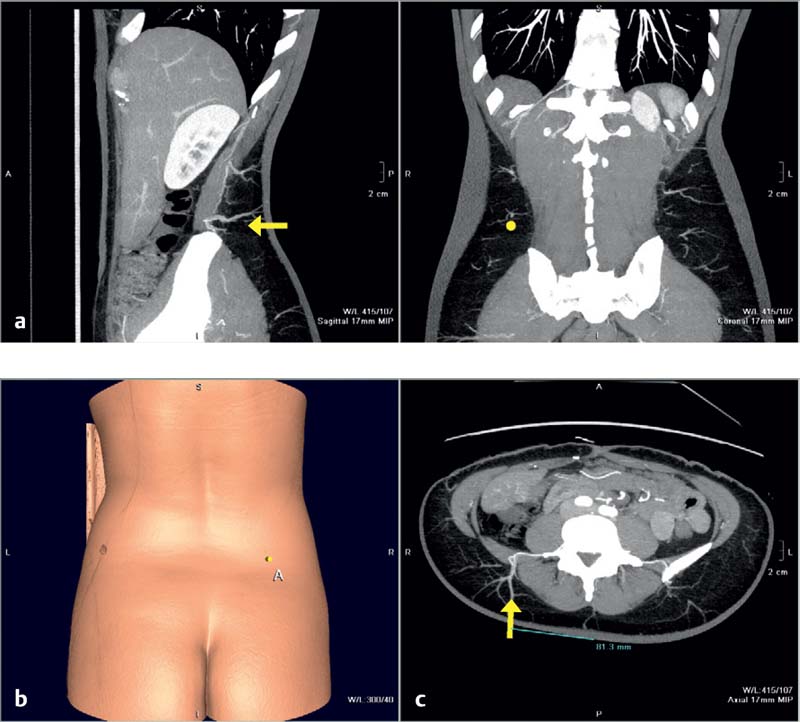

Before surgery, the size, position, and course of the lumbar perforators is checked on a preoperative computed tomography (CT) or MRA scan. The patient should be positioned face down for the scan, so that the gluteal/lumbar perforators are not compresses. The X-axis is provided either by a horizontal radiopaque marker or by the height of the iliac crest ( Fig. 8.4 ). The lowermost lumbar perforator (L4), crossing the posterior iliac crest, is usually preferred to enable positioning of the scar as low as possible.

In a study of seven fresh cadavers injected with lead oxide, we performed three-dimensional (3D) angiography to capture the distribution, size, and course of the lumbar artery perforators, which arise from the paired lumbar arteries (L1, L2, L3, and L4)23 ( Fig. 8.2 ). Most pairs pass posterior to the quadratus lumborum, but some take a route through the muscle. The L1 to L3 arteries course between quadratus lumborum and the erector spinae muscles, whereas the L4 vessels generally pass anterior to quadratus lumborum. Once the lumbar arteries pass the lumbosacral fascia, they branch into smaller vessels supplying the lumbar integument. We observed that the individual perforator anatomy was quite variable, but in general the L4 perforators were often septocutaneous, whereas the L1 perforators were mostly musculocutaneous. Individual perforator anatomy was highly variable but septocutaneous perforators usually passed between the quadratus lumborum and erector spinae. Computed tomography angiography (CTA) shows the 3D course of lumbar artery perforators. More perforators arise from the L1 and L4 than from L2 and L3. Perforators measure ~1 mm in diameter where they penetrate the lumbosacral fascia ( Fig. 8.3 ).